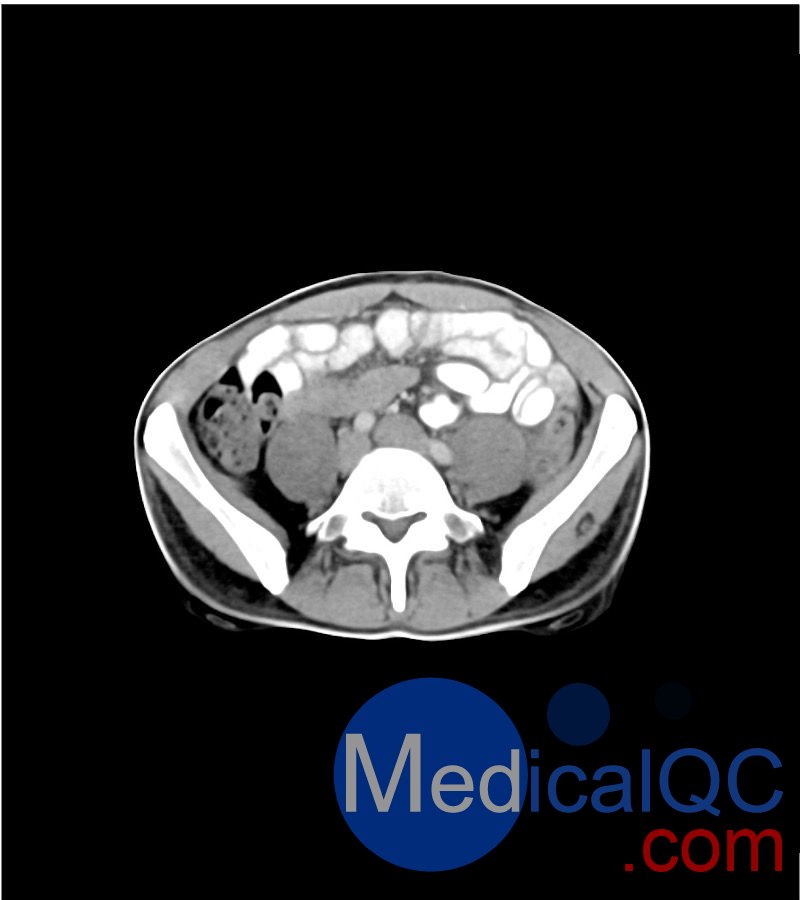

WEK-5501男性腹部模體,WEK-5501男性骨盤模體可模擬門靜脈期的腹部和盆腔增強掃描效果,掃描范圍覆蓋第一腰椎至?xí)巺^(qū)域。

該體模右側(cè)設(shè)有髂淋巴結(jié)腫塊(模擬病灶)。

1. 可對脈管系統(tǒng)、骨骼及軟組織進行逼真模擬,涵蓋的器官包括肝臟、膽囊、胰腺、脾臟、腎上腺、腎臟、胃、小腸、結(jié)腸、膀胱及前列腺。

2. 右側(cè)設(shè)有髂外淋巴結(jié)腫塊(模擬病灶)。

WEK-5501男性腹部模體,WEK-5501男性骨盤模體成像效果圖: